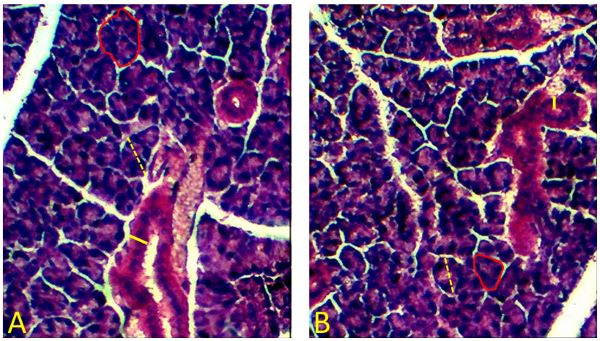

Table 1 shows the results of the morphometric analyses for the three major salivary glands. The parotid gland’s acinar diameters and ductal thicknesses were significantly smaller in the T group than in the C group (Figure 1). No further differences were found regarding the other morphometric parameters of parotid glands, nor for the morphometric parameters of sublingual (Figure 2) and submandibular glands (Figure 3).

Figures 1, 2, and 3 present photomicrographs of the parotid, submandibular, and sublingual salivary glands, respectively.

To the best of our knowledge, this study is the first to describe the toxicological effects of Clonazepam on the salivary glands of pregnant mice. The main finding was that this drug induced alterations in morphometric parameters of the parotid glands of pregnant mice exposed to the drug. Likely, the morphometric alterations described for the pregnant animal model used also occur in humans, due to the similar constitution of the salivary glands between the species. In both humans and mice, the parotid glands are composed of serous acini, the submandibular glands of mixed acini, and the sublingual glands predominantly of mucous acini (Li et al., 2011). Furthermore, it is possible that these morphological alterations are associated with functional alterations, for instance, in the production and secretion of saliva (Rinaldi et al., 2015).

The effect of benzodiazepines on the salivary glands of rodents has already been described in the literature. In one study, the authors found that benzodiazepines acted directly on acinar cells in rodent parotid glands by inhibiting the release of amylase (Okubo & Kawaguchi, 1998). Although there are no previous studies in the literature describing the results of the morphometry of acini in major salivary glands as a result of exposure to benzodiazepines, a reduction in the number of acinar cells in parotid glands in rats was found as a result of chronic exposure to two benzodiazepines, Midazolam and Lorazepam (Rinaldi et al., 2015). Moreover, it was shown that the chronic use of Midazolam was able to induce apoptosis of acinar cells (Rinaldi et al., 2018). Furthermore, Diazepam, also a benzodiazepine, has been shown to induce atrophy in parotid gland acini in rodents (Rinaldi et al., 2015).